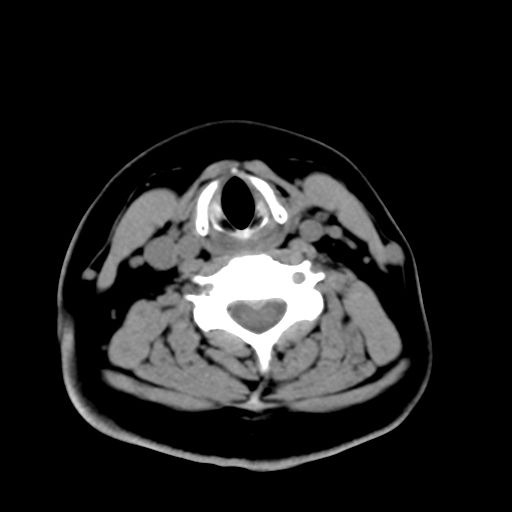

标题: CT25491:女,55岁,发现左侧甲状腺肿块一个月。 [打印本页]

标题: CT25491:女,55岁,发现左侧甲状腺肿块一个月。

女,55岁,发现左侧甲状腺肿块一个月,彩超示:甲状腺多发结节伴左叶结节液化。

腺瘤囊变

考虑左侧甲状腺腺瘤囊变。